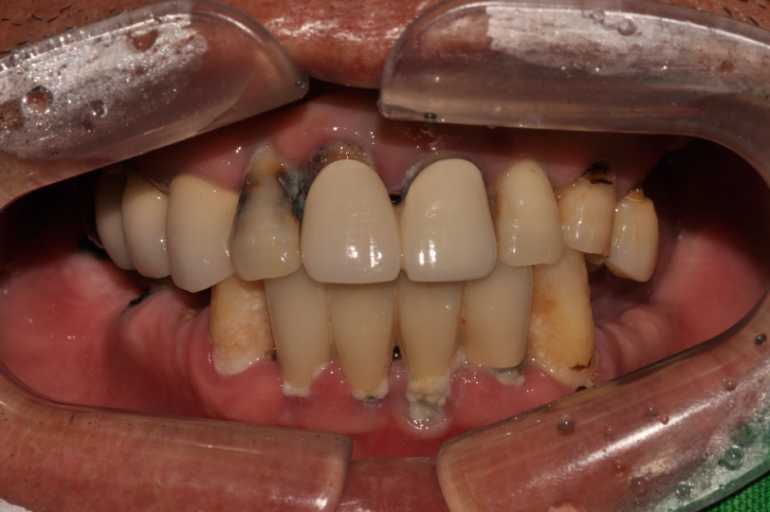

#무치악 임플란트 환자 사례 : 기존 치아의 염증 상태로 인해 치료 시작일 때, 잔존치 전체 발치 + 상악동거상술(양쪽) + 뼈이식다수 + 임플란트 픽스처(뿌리) 17개 식립